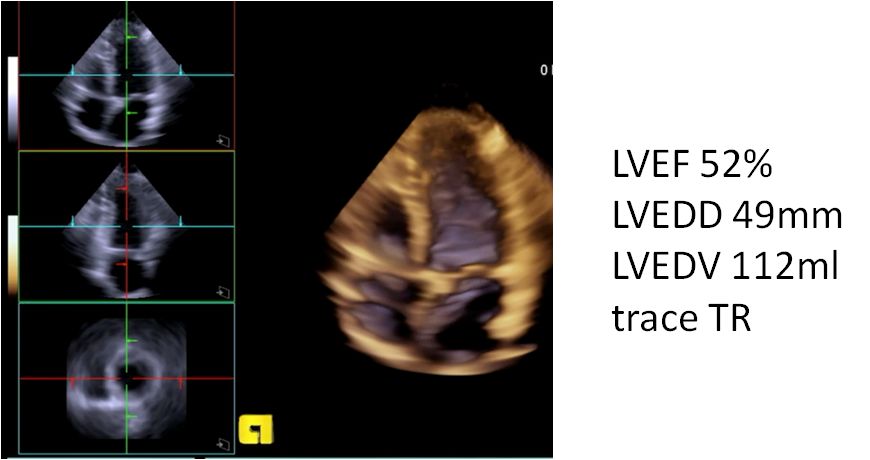

▶▷ 2018年10月29日-31岁男性,心力衰竭入院